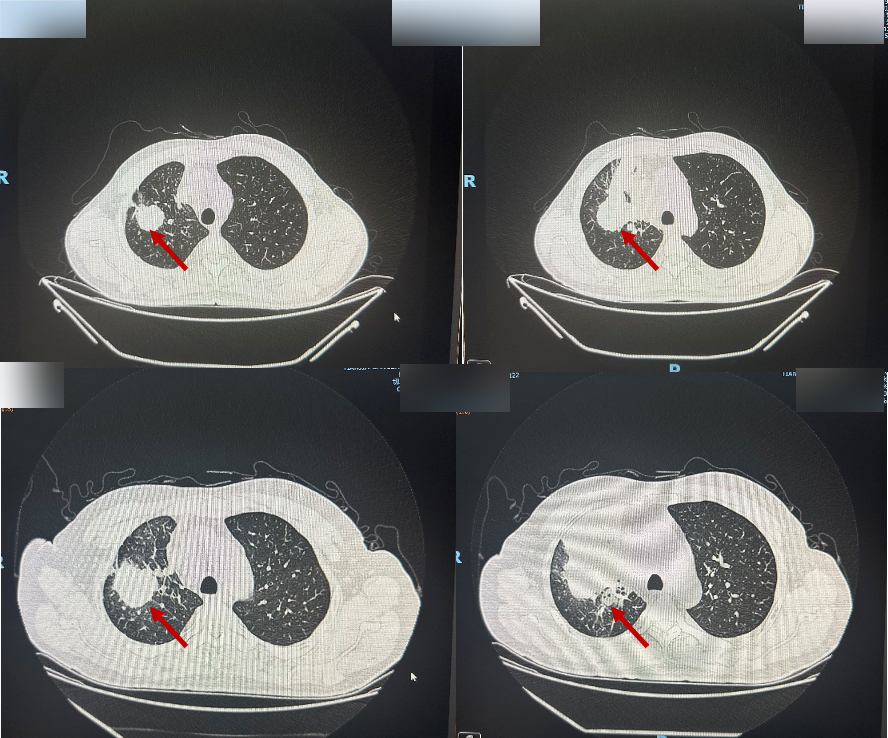

复查胸部CT(2024-10-09)示:与2024-08-08胸部CT检查相比,右肺上叶及右肺门软组织肿物范围较前增大;右肺上叶阻塞性改变较前加重;右肺门及纵隔内部分淋巴结较前增大。

图2 胸部CT(上:2024-08-08,下:2024-10-09)

头颅增强MRI(2024-10-22)示:1.右侧额叶结节,考虑转移瘤伴瘤周水肿;2.双侧额顶叶及侧脑室周围多发异常信号影,考虑脱髓鞘改变。

疗效评估:PD。临床分期:cT2N3M1 Ⅳ期。

PFS2:2个月。